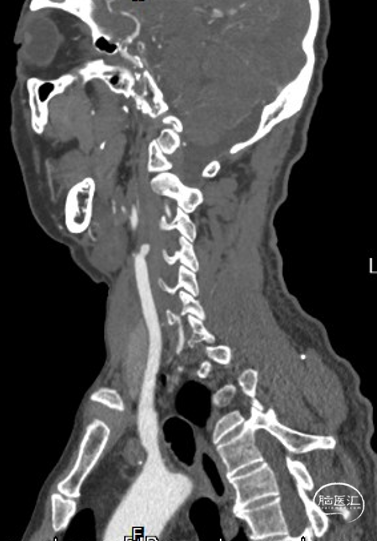

头颈部CTA